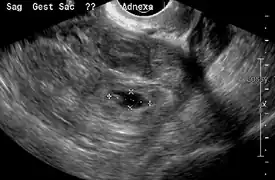

A "blob sign", which consists of the ectopic pregnancy. The ovary is distinguished from it by having follicles, whereof one is visible in the field. This patient had an intrauterine device (IUD) with progestogen, whose cross-section is visible in the field, leaving an ultrasound shadow distally to it.

Ultrasound image showing an ectopic pregnancy where a gestational sac and fetus has been formed